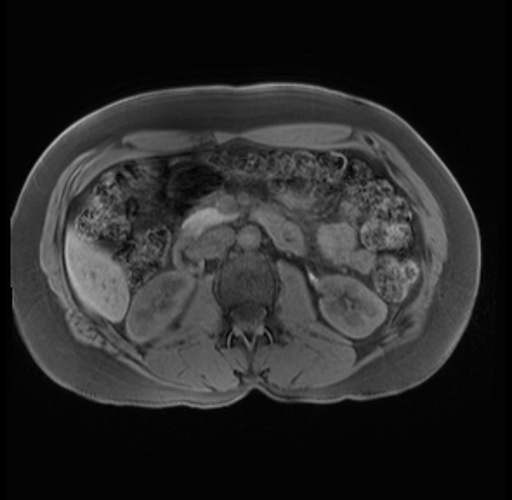

Imaging Analysis

Look through the patient's CT scan to identify any areas of concern for the necessary procedure.

Based on your CT findings, which issue(s) are present and would give reason for "planned slowing down moment(s)" in this case?

Considering a standard distal pancreatectomy procedure, what step(s) of the operation would you do differently in this case?